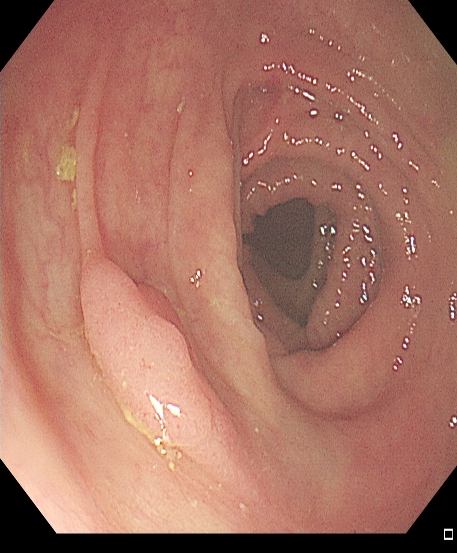

适用于不同大小隆起型病变Ⅰp型、Ⅰsp 型以及小型(<2 cm)Ⅰs型(具体分型标准可参照内镜发现消化道早癌,分型太多不知道怎么判断?这篇文章讲清楚了)病变的切除。小型Ⅰp型病变,圈套切除相对简单,可采用冷或热圈套切除,切除时应在保证完整切除病变同时,保留一定长度的蒂部或与肠壁保持一定距离,收紧圈套后,应抖动圈套器,观察有无周围正常肠黏膜一并套入,防止损伤肠壁。

图2 小型Ⅰsp 型病变热圈套切除示意图